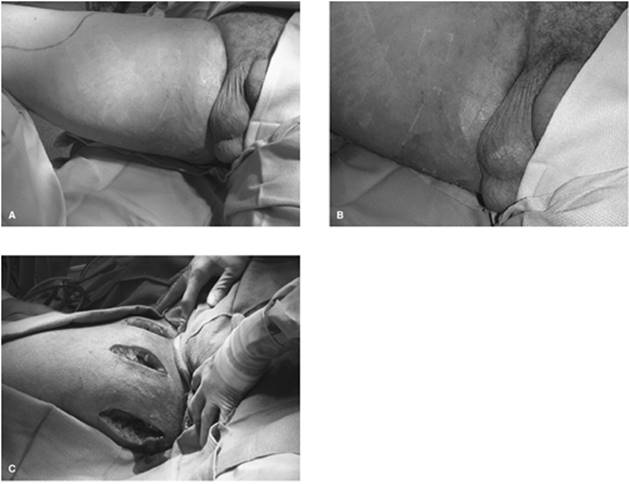

d. Fournier's gangrene (idiopathic gangrene of the penis and scrotum) (21): Although first described in 1764 by Baurienne, this entity received its name from a French venereologist, Jean-Alfred Fournier. In 1883 he presented a case of gangrene of the perineum in an otherwise healthy young man. In 95% of cases, an identifiable cause can be found, with the disease process originating from the anorectum, the urogenital tract, or the skin of the genitalia. Anorectum causes include malignancy, diverticulitis, or appendicitis. Urethral injury, urethral stricture, urogenital manipulation, or infection can initiate Fournier's gangrene, whereas cutaneous conditions like hidradenitis suppurativa or trauma can be precursors. In addition to local predisposing conditions, systemic factors such as leukemia, systemic lupus erythematosus, Crohn's disease, HIV, or other conditions of immunodeficiency may predispose one. Other predisposing comorbidities associated with Fournier's include obesity, cirrhosis, vasculitides of the perineum, steroid use, and diabetes. On exam the typical Fournier's patient will be an elderly male in his sixth or seventh decade of life with one or more of the above comorbidities. Clinically, this patient may have a history of fever and lethargy for approximately 1 week. Pain, tenderness, and erythema of the genitalia and overlying skin will progress to a dusky appearance, ultimately with purulent-appearing drainage.

Figure 107.13. A-C: Fournier's gangrene involving the perineum but sparing the penis and testicles. Wide debridement has been performed.

Although wide local debridement may be the classical therapy for cases of necrotizing soft tissue infections (Table 107.5), initially, diagnostic surgical exploration can be limited (26,27). A series of small incisions under local anesthesia can be performed to delineate the extent and presence of muscle or facial necrosis. In addition, frozen sections of tissue specimens obtained can establish the diagnosis. However, once the diagnosis is confirmed, there exists no role for conservative debridement or incision and drainage. In the case of Fournier's gangrene, an understanding of the anatomic relationship between the perineum and abdominal wall is important. Below the area of the inguinal ligament, Scarpa's fascia blends into the Colles's fascia, which is contiguous with the dartos fascia of the penis and scrotum (Fig. 107.13A–C). This allows a potential space to exist between the Scarpa's fascia and abdominal oblique musculature, contributing to a potential spread from the perineum to the anterior abdominal wall. Due to Buck's fascia, a deep fascia that covers the corpora and anterior urethra, and due to the retroperitoneal blood supply to the testis, the penis and testicles may be spared.

The two most common pitfalls with a necrotizing soft tissue infection are diagnostic delay and inadequate debridement. Excision of nonviable areas should be early and aggressive, with repeat debridements performed until the local process has been controlled. The use of electrocautery will aid in reducing the considerable operative blood loss if the area of involvement is extensive. With perineal involvement, fecal diversion via colostomy allows for less contamination of the wound site. With urogenital involvement, continued use of a urethral catheter is safe; occasionally suprapubic cystostomy will be necessary. In the case of Fournier's gangrene, the testicles are usually spared. To prevent dessication they are usually placed in a surgically made subcutaneous pocket. If not viable, orchiectomy is performed. In all cases of NF, vacuum-assisted closure devices have shown great promise in decreasing time to grafting and closure of the debrided area (Fig. 107.9B).